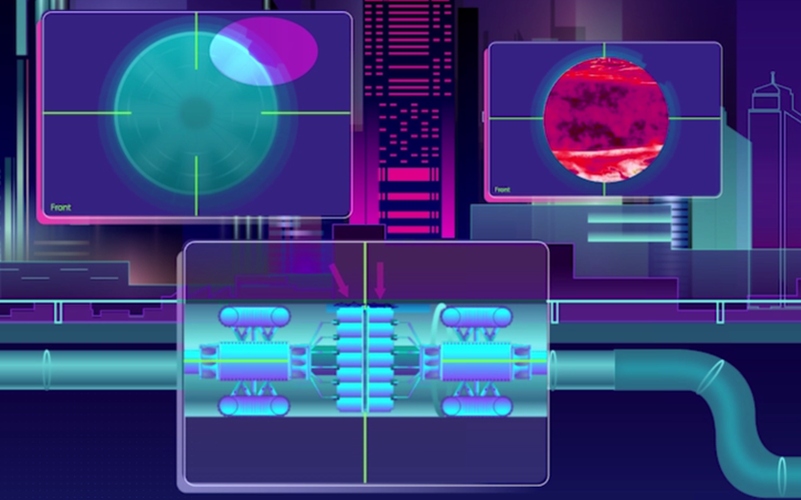

Projenin geliştiricisi profesör James Covington, yakın gelecekte yapay zeka ile bütünleşik olarak gelişecek testlerin gebelik sürecinde birer standart haline gelmesini bekliyor. Dahası Covington, testlerin gelişip çok erken aşamada genetik sorunları da tespit etmesi bekliyor. “Testin uygulanması ve yorumlanması için herhangi bir bilgi birikimi gerekmiyor. Cihazı fişe takıyorsunuz. Ardından her şeyi o hallediyor. Teknisyen gerektirmediği için yaygınlaşmasını umuyoruz. Üstelik sonuçlar sadece birkaç dakikada geliyor.”